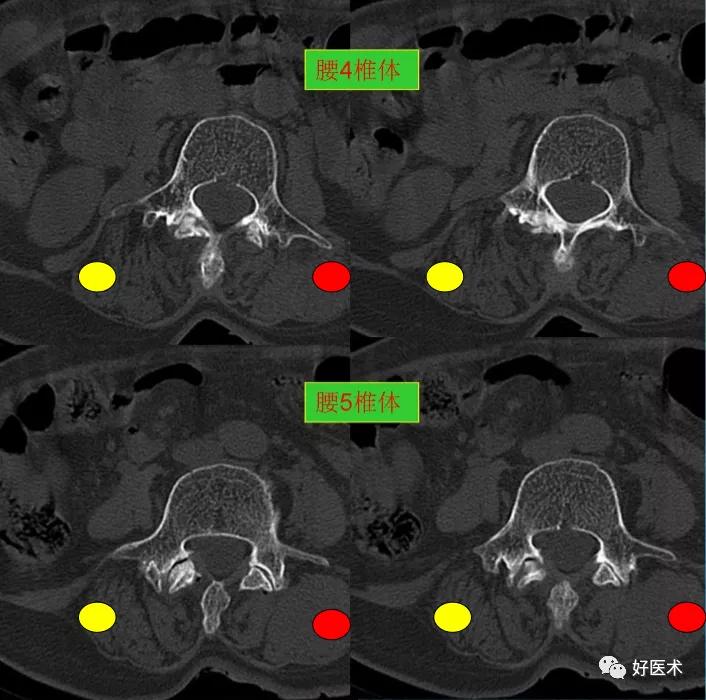

CT图像,腰椎常规采用序列扫描,腰椎体2层,腰间盘4层,层厚2.5mm,一般扫描范围包括腰2--骶1椎体及所属间盘。

腰4、5椎体及附件骨质未见著变。

发现了什么?左侧竖脊肌较右侧明显肿胀饱满, 肌间脂肪间隙消失!!